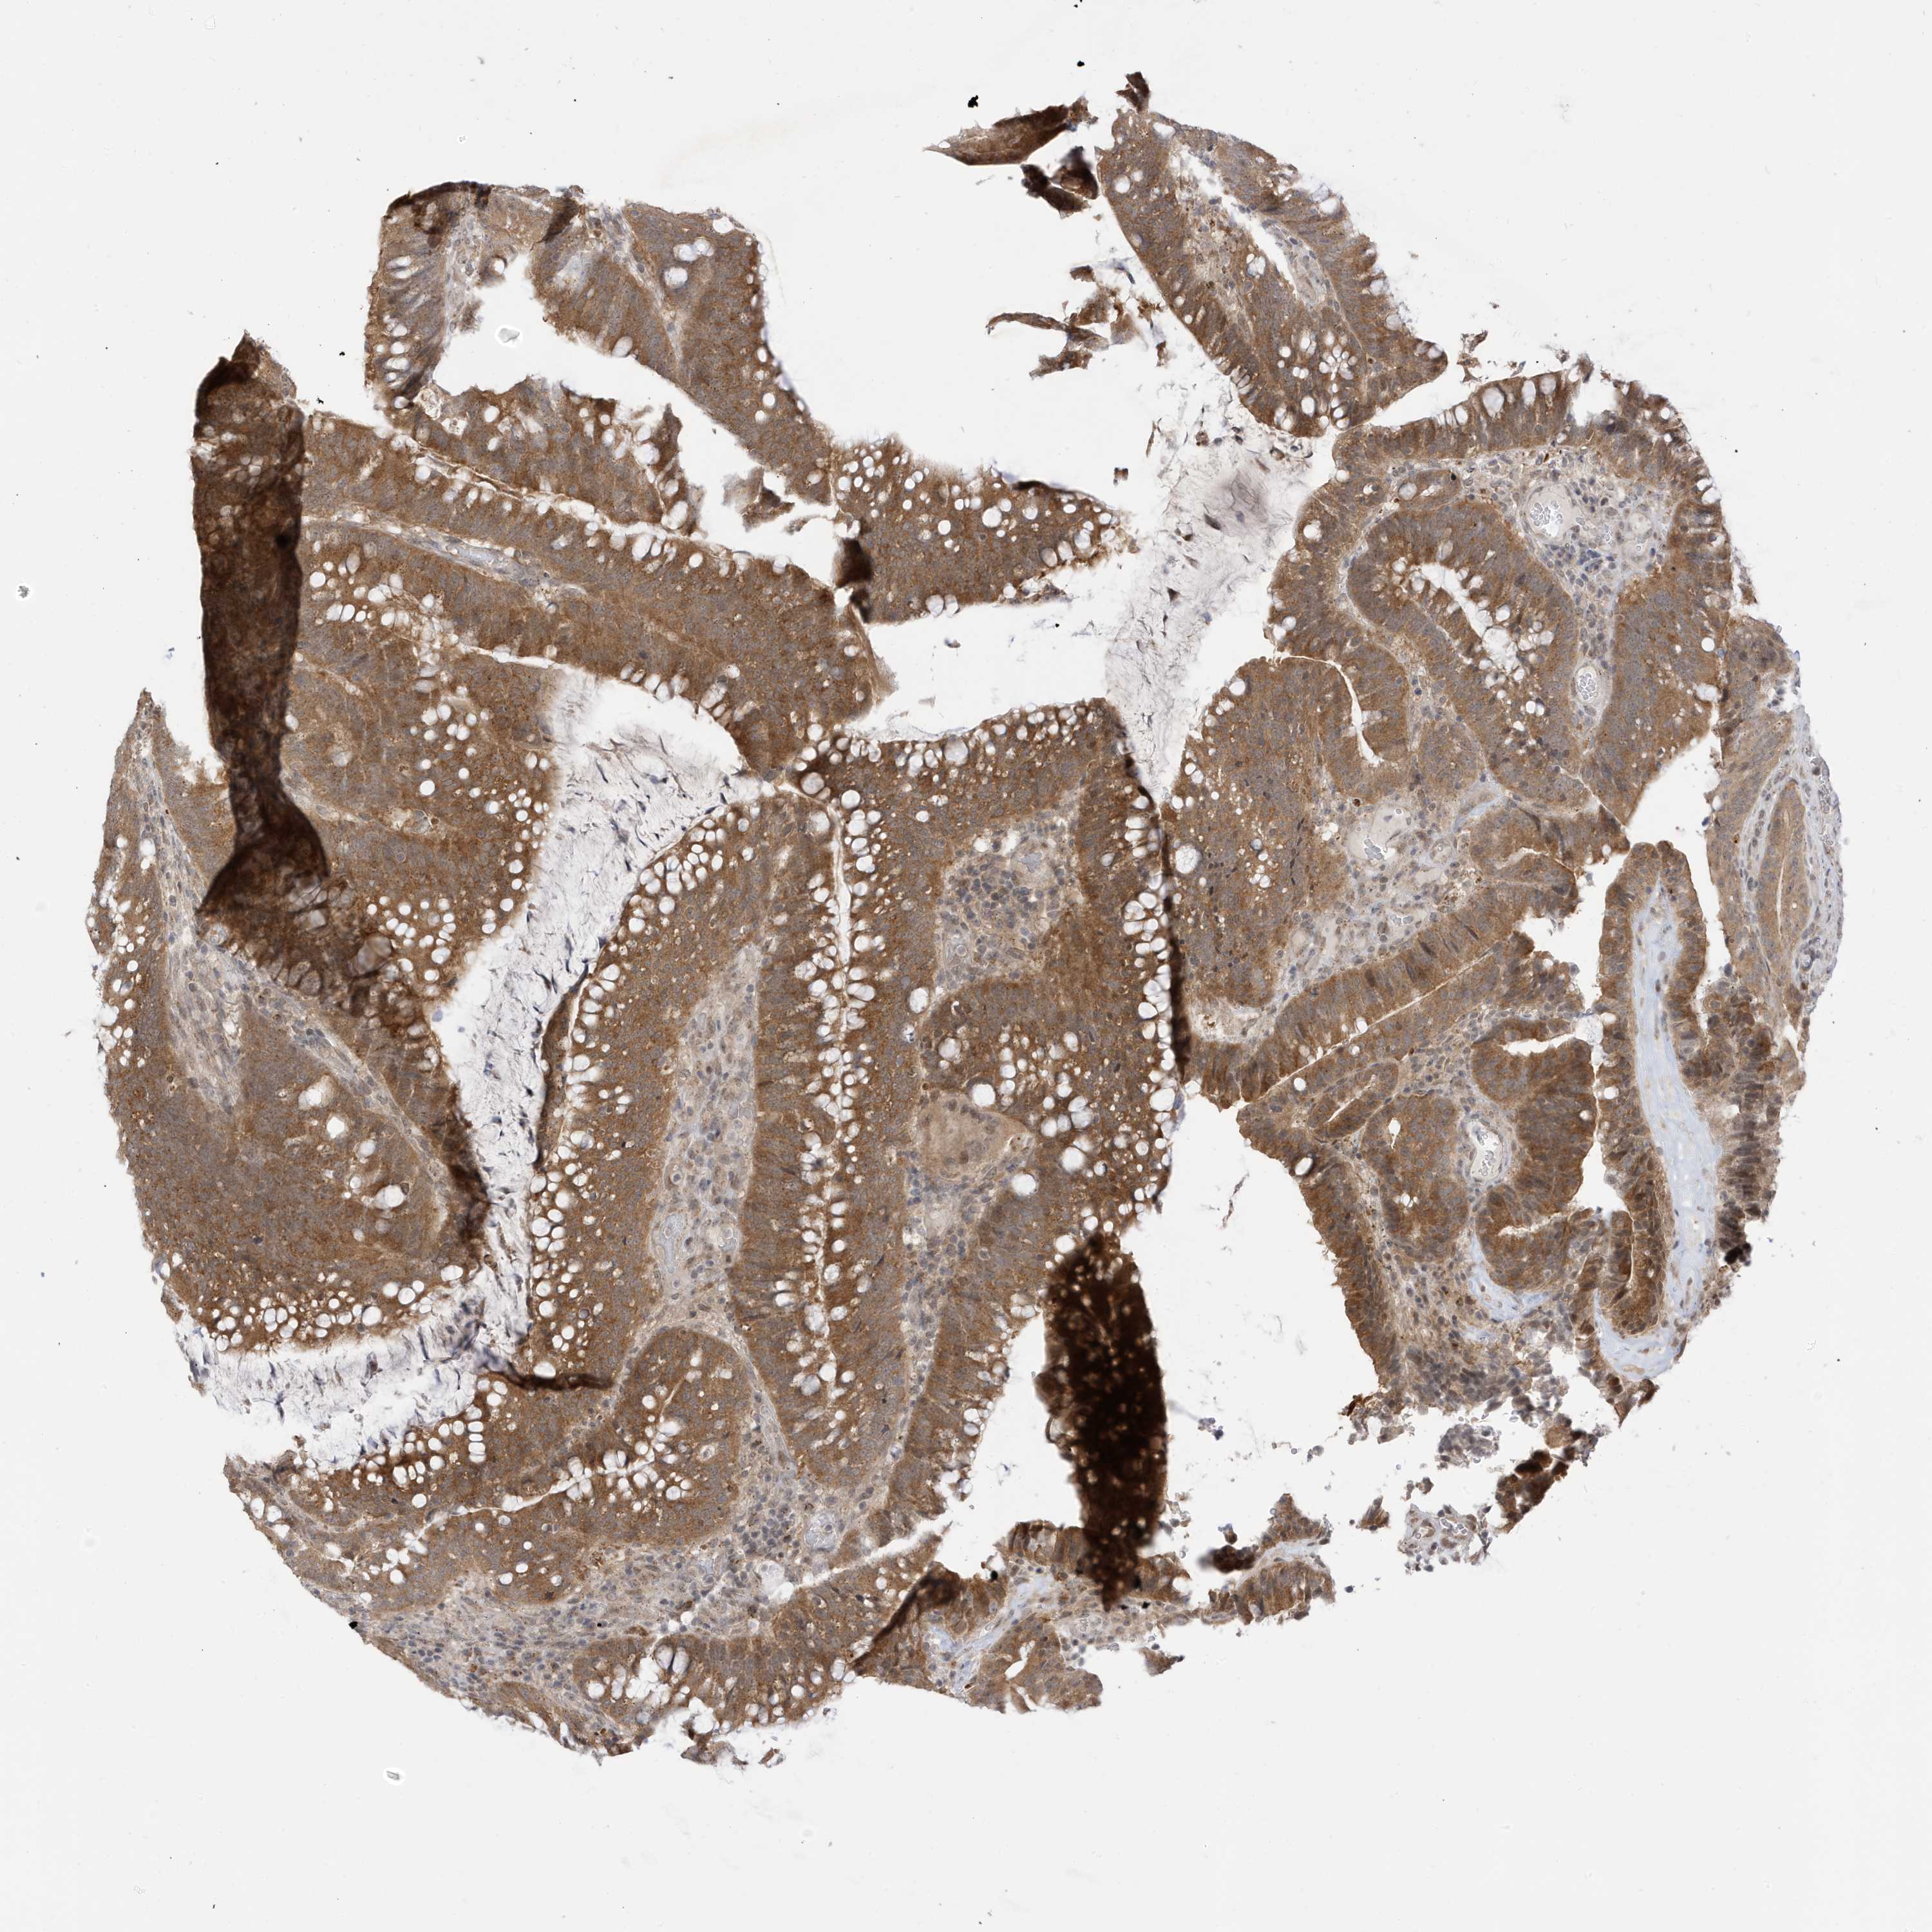

CANCER COLORECTAL CANCER Show tissue menu

Colorectal cancer

Human cancer

Colon adenocarcinoma